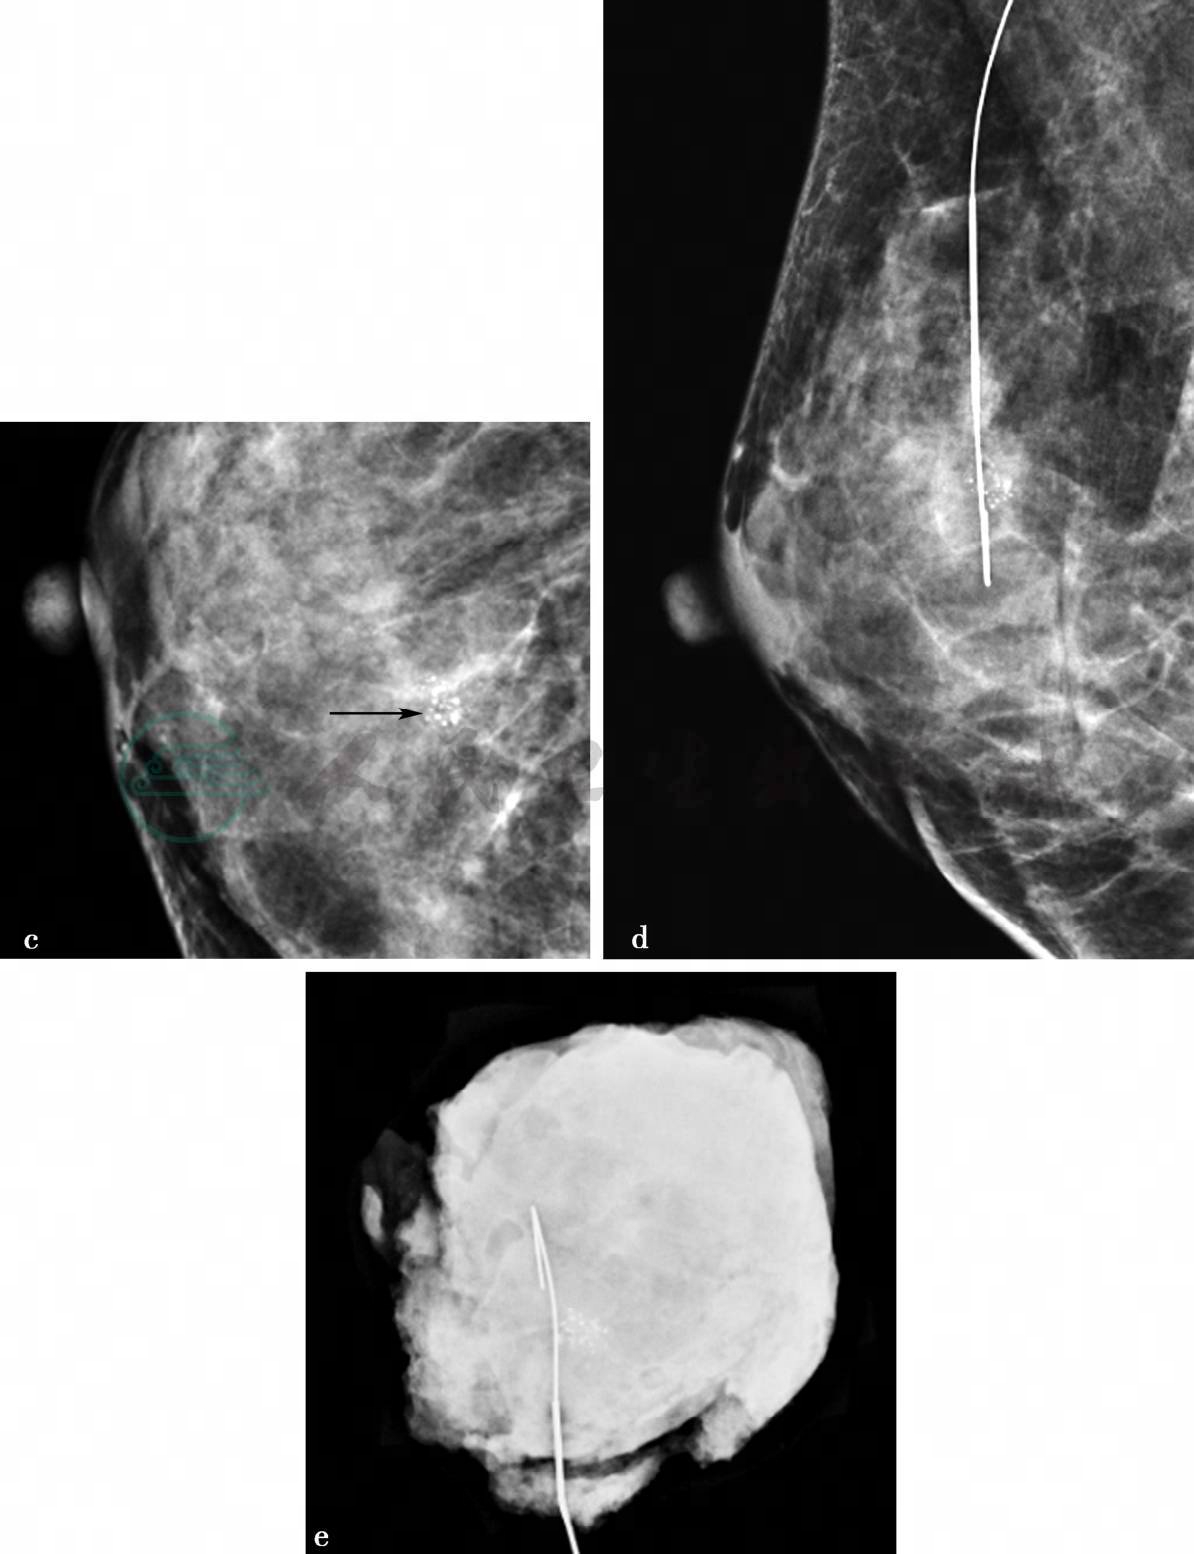

图1 图1a,右乳X线头尾位。图1b,右乳X线内外斜位。图1c,右乳X线头尾位钙化局部放大。图1d,X线导向下右乳钙化区域金属丝定位图像。图1e,右乳病变切除术后标本X线。X线显示双乳呈不均匀致密型乳腺,右乳内上方可见成簇不均质钙化,范围约0.8cm×0.7cm(图a、b、c箭头所示),其余未见明显异常

图2 图2f,右乳病变二维超声图。图2g,右乳病变彩色多普勒血流图。超声显示右乳稍内上方局限低回声区,范围约0.9cm×0.6cm,边界不清,内部回声不均匀,其内可见点状强回声。图2g,CDFI示可见较粗大血流信号